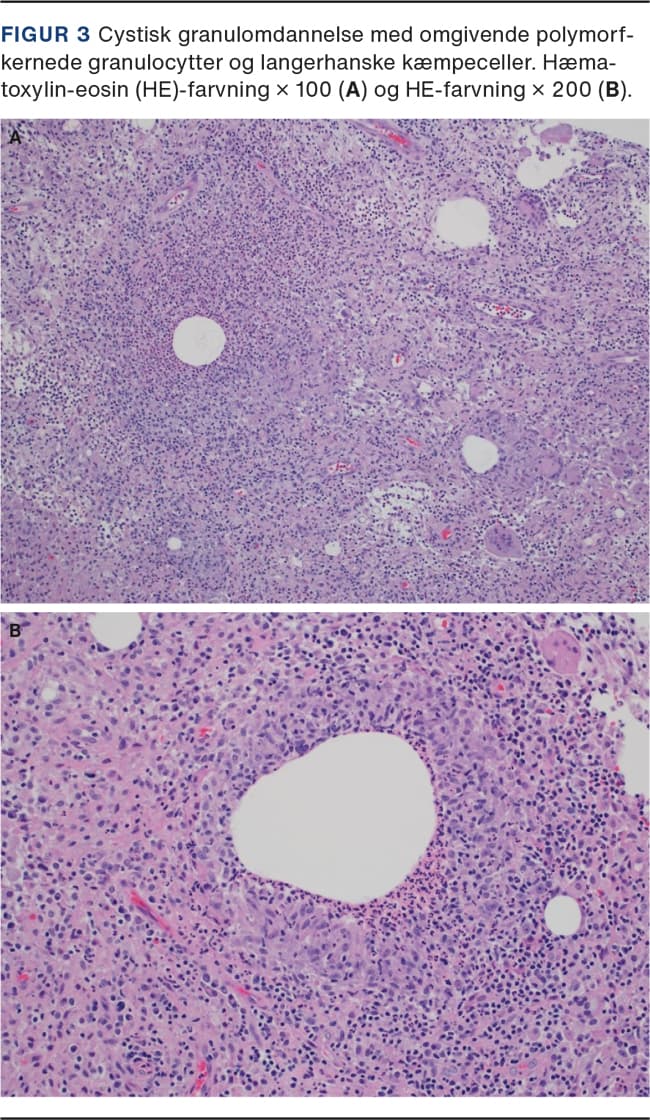

Granulomer er en ansamling af epiteloide histiocytære celler. Ved IGM domineres det histologiske billede af granulomer uden kaseøse nekroser som lobuli og bestående af epiteloide histiocytter, Langerhans kæmpeceller, plasmaceller, lymfocytter og evt. eosinofile granulocytter. Abscesdannelse kan forekomme. Bakterier, svampe og parasitter påvises ikke, og vaskulitis ses ikke. Ved CNGM findes lobulocentrisk granulomdannelse med et eller flere centrale mikrocystiske hulrum omgivet af en bræmme af neutrofile granulocytter [13](Figur 3)[14]. I visse tilfælde ses der grampositive stave i hulrummene, og i andre tilfælde kan der ikke påvises noget infektiøst agens. Det er vigtigt, at man tager flere biopsier ved klinisk mistanke om GM, da der er risiko for negativt biopsisvar.